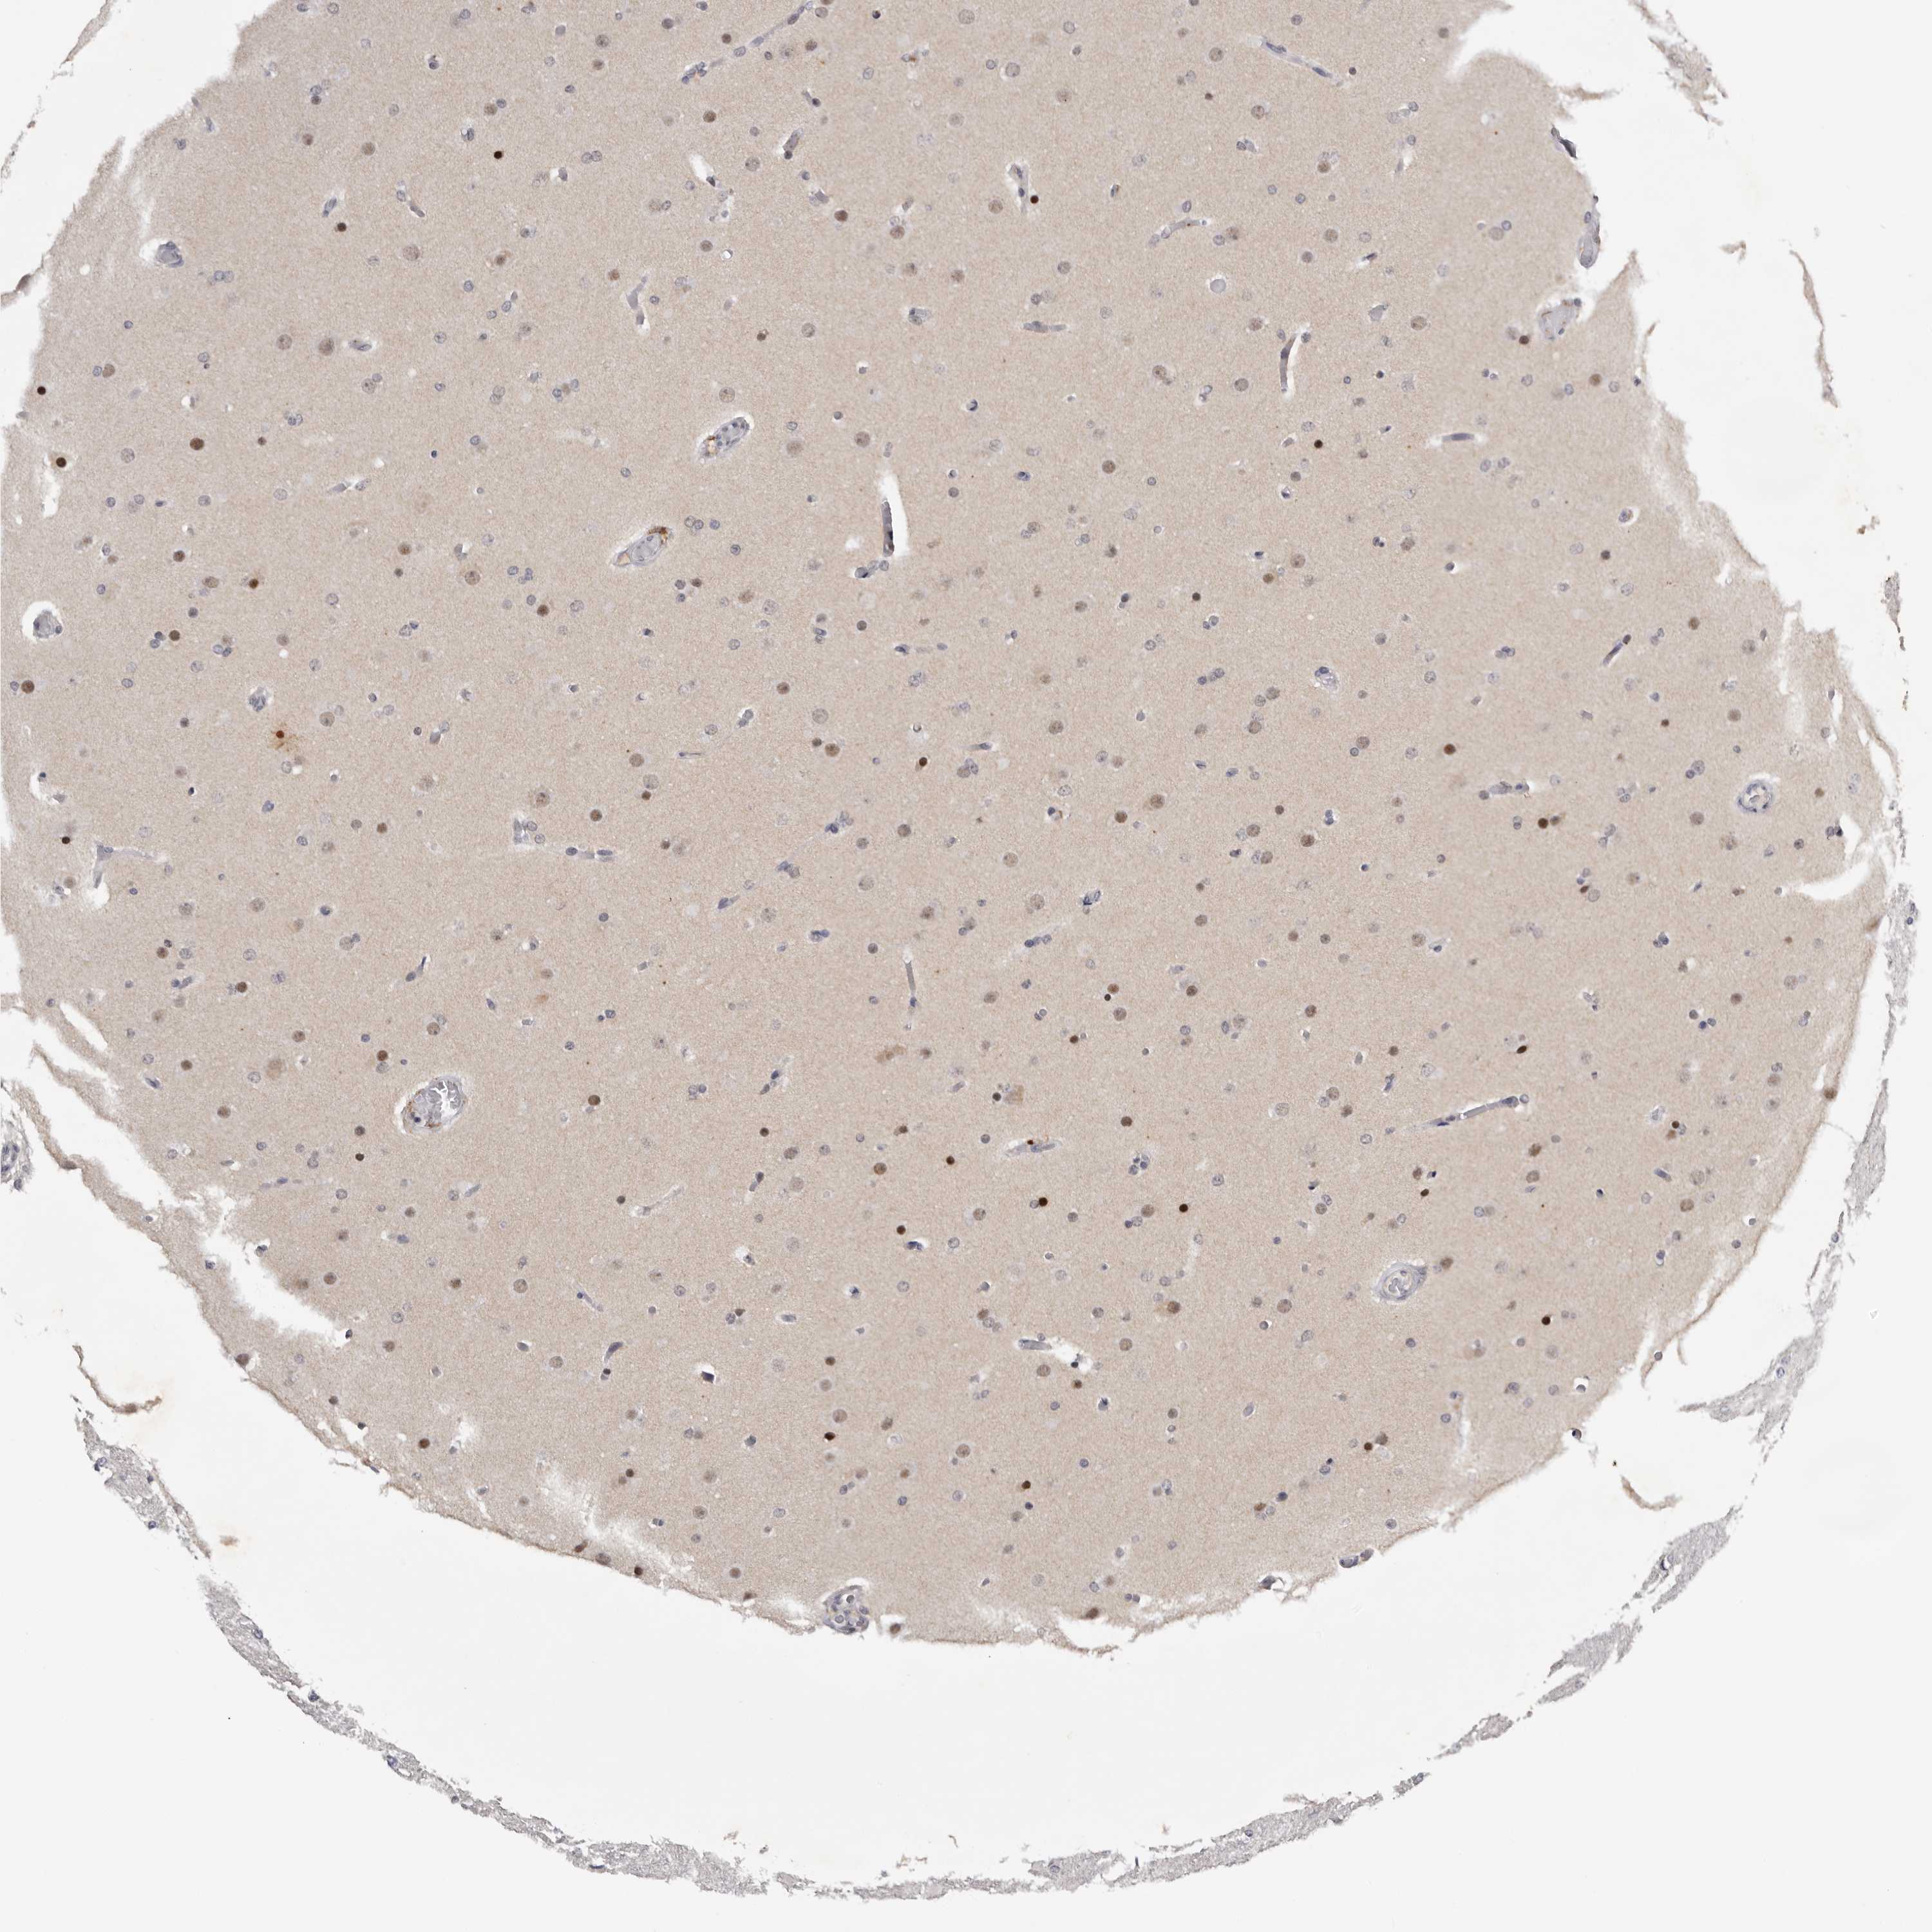

GLIOMA - Protein expressioni

A mouse-over function shows sample information and annotation data. Click on an image to view it in a full screen mode. Samples can be filtered based on level of antibody staining by selecting one or several of the following categories: high, medium, low and not detected. The assay and annotation is described here.

Note that samples used for immunohistochemistry by the Human Protein Atlas do not correspond to samples in the TCGA dataset.

Antibody stainingi

Antibody staining in the annotated cell types in the current human tissue is reported as not detected, low, medium, or high, based on conventional immunohistochemistry profiling in selected tissues. This score is based on the combination of the staining intensity and fraction of stained cells.

Each image is clickable and will lead to virtual microscopy that enables deeper exploration of all samples and also displays staining intensity scores, fraction scores and subcellular localization as well as patient and tissue information for each sample.

Antibody HPA023081

Antibody HPA023103

Antibody HPA024795

Glioma, malignant, High grade

Glioma, malignant, Low grade